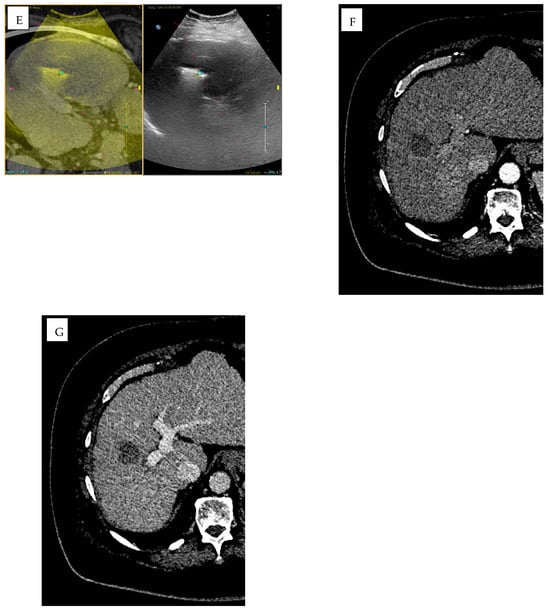

AI-driven image guidance systems such as XperGuide (Version 3.5.1, Philips Allura Xper FD20, Philips Healthcare), improve the precision of percutaneous procedures by delivering real-time three-dimensional needle guidance for percutaneous interventions [,] (Figure 3). XperCT software (Version 3.5.1, Philips Allura Xper FD20, Philips Healthcare) can be used to predict ablation volume [].

Figure 3.

A 61-year-old man with rectal adenocarcinoma previously treated with surgery, adjuvant chemotherapy, and radiotherapy. Pre-procedural MRI, including axial (A) and sagittal (B) T2-weighted images, (C) T1-weighted post-contrast image, and (D) diffusion-weighted imaging (DWI) with (E) apparent diffusion coefficient (ADC) map, together with (F) 18F-FDG PET/CT, demonstrate a heterogeneous mass in the presacral region consistent with local disease recurrence (red arrows). (G–I) Intra-procedural cone-beam CT (CBCT) in axial (G), coronal (H), and sagittal (I) planes obtained using XperGuide software (Philips Healthcare) for cryoablation probe placement (purple arrows), and XperCT (Philips Healthcare) for ablation zone prediction (purple and yellow circles).

XperGuide and XperCT are utilized in a wide variety of clinical settings, particularly in liver, lung, and renal tumor interventions. In liver tumors, particularly those located in the subphrenic region or near vital structures, their precise needle placement capabilities reduce the need for intraoperative patient repositioning and significantly lower the risk of complications such as infection and misplacement []. Similarly, in lung interventions, XperGuide enhances the accuracy of needle navigation in complex thoracic anatomies, thereby decreasing the number of passes required, reducing the risk of pneumothorax, and minimizing procedural trauma and subsequent interventions [,]. For renal tumors and spinal metastases, XperCT improves lesion visibility in areas where MRI may be limited, enabling more precise treatment planning and needle placement [,].

Both XperGuide and XperCT use intelligent algorithms for real-time trajectory optimization, motion compensation, and collision detection, but are not fully dependent on deep learning. These features enhance the safety of procedures by considering the patient movements—such as breathing—and avoiding important structures. Moreover, ongoing research seeks to integrate ML models that predict lesion response based on ablation geometry, suggesting optimal energy settings tailored to specific tissue characteristics. This would further personalize interventions, improving the likelihood of complete tumor ablation while minimizing damage to surrounding healthy tissues [,].